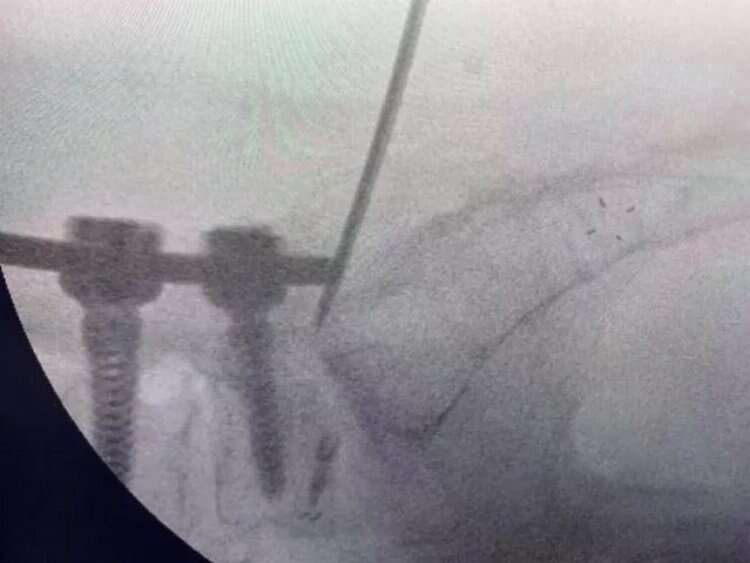

Hekimler; kırıklar, skolyoz eğrilikleri, tümörler, kanal daralması gibi ameliyatlarında vidalarla omurları desteklemede bulunuyor. Ancak vidaların bulunduğu omurlar düşme, çarpma gibi kazalar nedeniyle kırılabiliyor. Bu duruma müdahale etmek için ise açık ameliyat gerekiyor. Beyin ve Sinir Cerrahisi Uzmanı Prof. Dr. Kemal Yücesoy, vidalı omurganın kırığına dünyada ilk kez transforaminal transdiskal yaklaşımla sement desteği yaptı.

Uzun süre, vidayı çıkarmadan kemik çimentosunu koyma konusunda çalışmalar yaptığını belirten Prof. Dr. Yücesoy, “Kapalı bel fıtığı ameliyatlarında iğneyle sinirin altına girerek izlediğimiz bir yol var. ‘Hastaların kemiğinin içine bu yoldan girilebilir’ diye düşündüm ve bunu da uygulamaya başladım. Bu yöntemde, hastaya lokal anestezi uyguluyoruz. Kıkırdağın olduğu bölümden diskin içine iğneyle girip oradan da kemiğin içine ulaşıyoruz ve çimentoyu koyuyoruz. Bu daha önce hiç uygulanmamış bir yol. Kırılmış vidalı bir kemiğe ilk kez o vidayı çıkarmadan kapalı yöntemle girip müdahale etmiş olduk” diye konuştu.